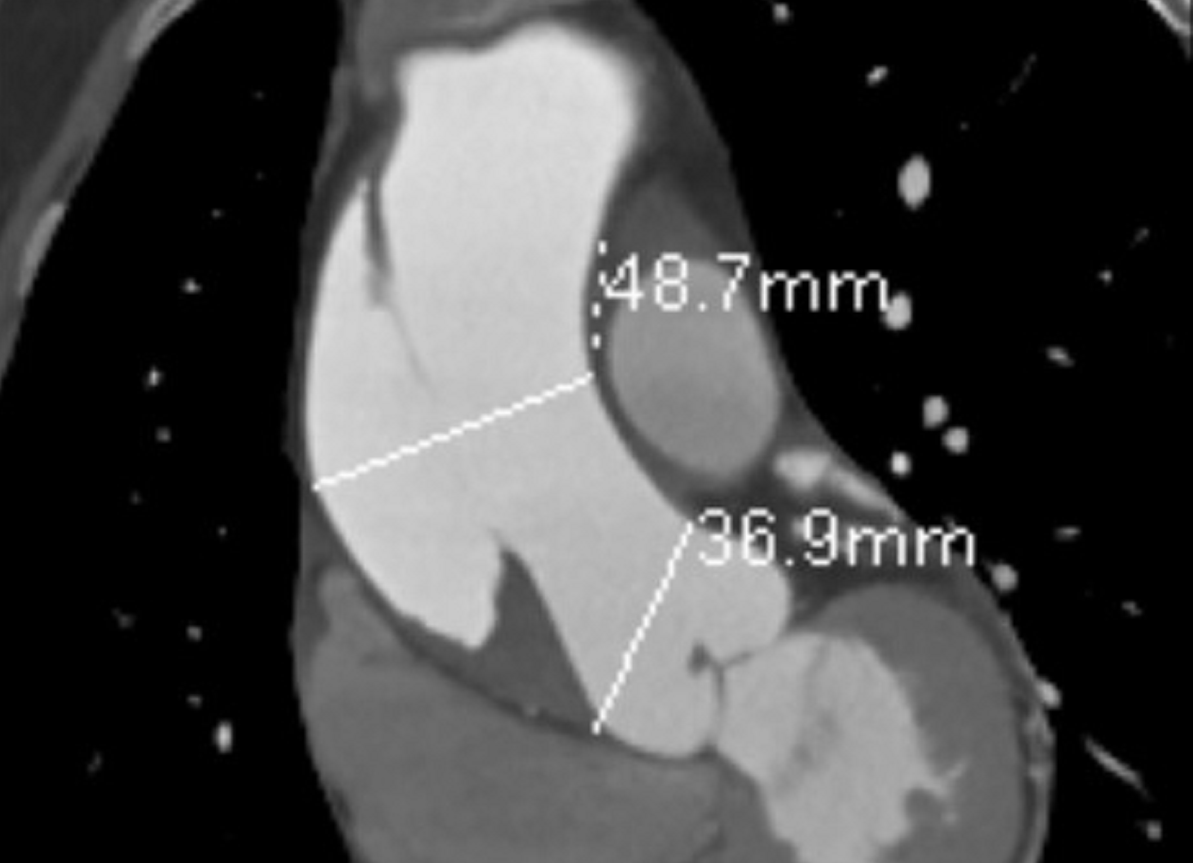

| Hình ảnh kiểm tra cho thấy vị trí lóc tách động mạch chủ rất nặng ở bệnh nhân |

Thời điểm nhập viện, ngoài biểu hiện đau ngực dữ dội, bệnh nhân còn bị đau lan ra sau lưng. Kết quả chụp CT-Scan động mạch chủ và các xét nghiệm cho thấy người bệnh bị lóc tách động mạch chủ ngực đoạn lên, thành động mạch chủ giãn lớn, kèm theo tình trạng tràn máu màng tim.